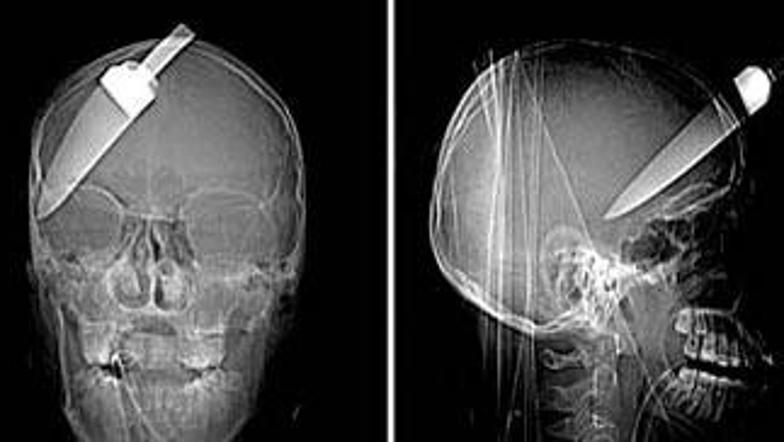

Rentgenski posnetki glave najstnika, na katerih je viden globok vbod v glavo, kažejo, da je lahko resnično srečen, da je še živ.

Zdi se kot dobro izdelana potegavščina, a ni. Rentgenski posnetki najstnikove glave, ki jih je razkrila britanska policija in na katerih je viden globok vbod v glavo, kažejo, da je lahko mladenič resnično srečen, da je še živ.

Šestnajstletnika so ranili, ko je skupaj z vrstnikom poskušal preprečiti rop prijatelja na avtobusnem postajališču v Južnem Londonu. Z nožem v glavi so ga takoj po nasilnem dejanju prepeljali v bolnišnico, kjer je čudežno preživel in je popolnoma zdrav.